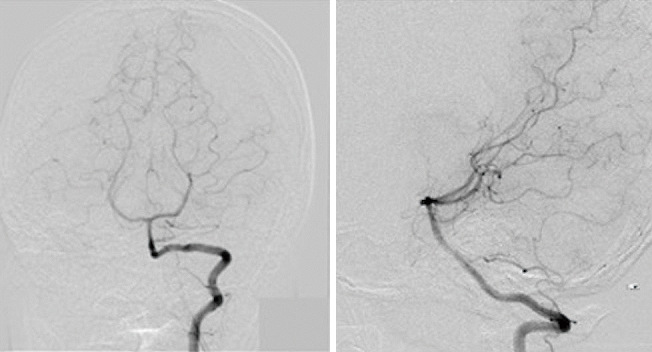

Coronavirus disease 2019 (COVID-19)-related intracranial hemorrhage (ICH) is believed to be associated with at least one known risk factor for ICH, such as hypertension, hyperlipidemia, diabetes mellitus, severe pneumonia, or anticoagulation therapy. However, in this study, we report a case of ICH in a 14-year-old boy with mild COVID-19 infection without pneumonia who had no such risk factors. The only abnormal laboratory finding was temporary depletion of vitamin K-dependent coagulation factors. This case indicates that COVID-19 infection may cause simultaneous asymptomatic intracranial microhemorrhages and temporary depletion of vitamin K-dependent coagulation factors. This temporary depletion might transform the intracranial microhemorrhages into symptomatic ICH.

与冠状病毒病 2019(COVID-19)相关的颅内出血(ICH)被认为至少与一个已知的 ICH 危险因素有关,如高血压、高脂血症、糖尿病、重症肺炎或抗凝治疗。然而,在本研究中,我们报告了一例 ICH 病例,患者是一名 14 岁男孩,患有轻度 COVID-19 感染,无肺炎,且无上述危险因素。唯一的实验室异常发现是维生素 K 依赖性凝血因子的暂时性耗竭。该病例表明,COVID-19 感染可能同时导致无症状性颅内微出血和维生素 K 依赖性凝血因子的暂时性耗竭。这种暂时性消耗可能会将颅内微出血转变为有症状的 ICH。